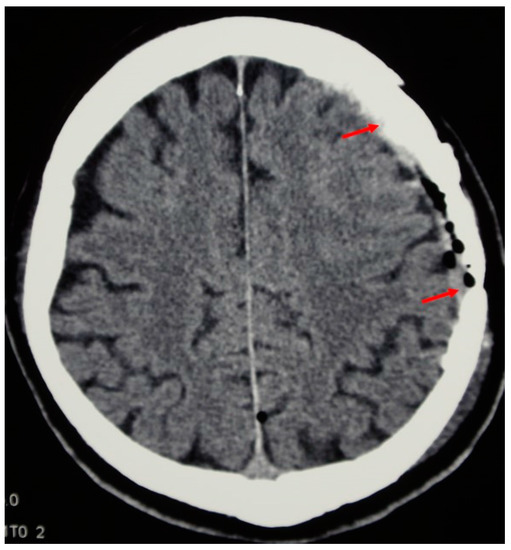

The day after the reconstruction, a control CT scan showed a good position of the implant with no displacement, deformation or fluid collection underneath. The rest of the postoperative course was uneventful. No complications were observed and no reoperation or revision was necessary, except for one patent from the tumour group, as mentioned above. At the discharge, there were no signs of cerebrospinal fluid leakage or infection and the wounds were healing by first intention.

During the follow-up at the outpatient department, three months after the reconstruction in the tumour and the vascular group and six months after the reconstruction in the trauma group, the wound was healed completely and the aesthetic result was excellent. No deformations were noticed and the patients reported no allergic reactions (Figure 5).

Figure 5. The follow-up CT scan shows the implant integration with the cranial bone (arrows denote both ends of the artificial flap).